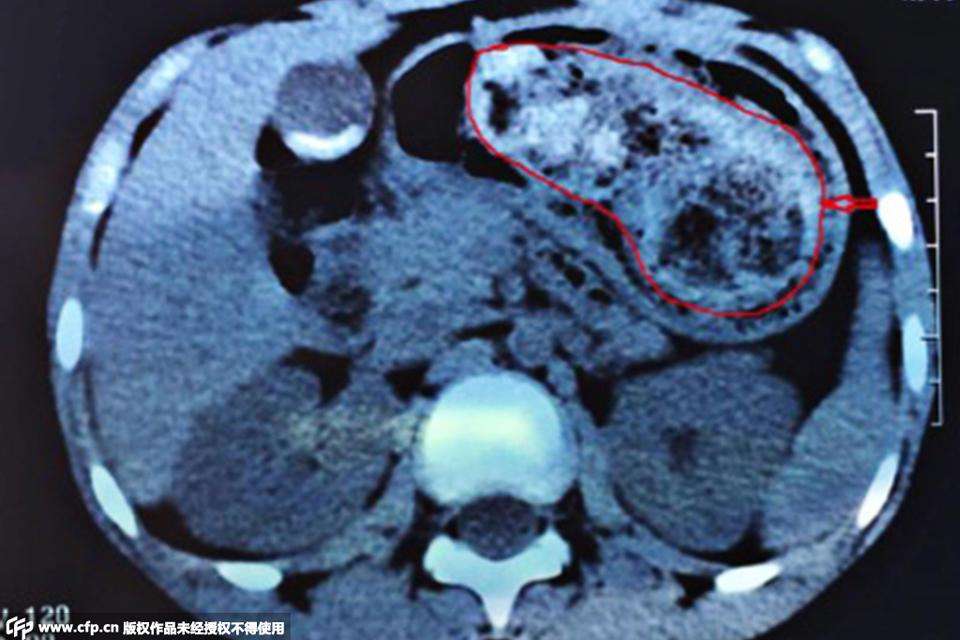

胃结石形成后,大多数病人有上腹不适、胀满、恶心或疼痛感;有些病人有类似慢性胃炎的症状,如食欲不振、消化不良、上腹部胀、钝痛、反酸、烧心;部分病人可合并胃溃疡;体积较大的胃结石,上腹部可有重压感及一定程度的梗阻表现,可引起黏膜损伤致溃疡及出血,严重者可导致穿孔和腹膜炎。如果怀疑是胃石症,胃镜检查是首选的检查方法,还可以选择上消化道造影和胃部B超等。